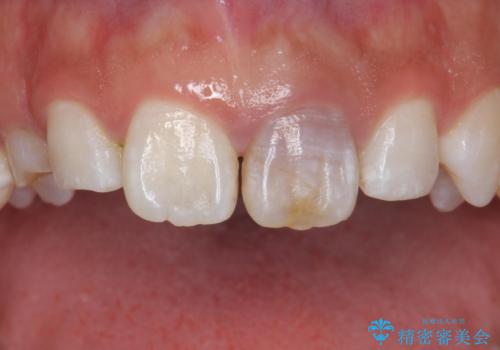

変色した前歯 ジルコニアクラウンでの修復

根管治療からのやり直しをした後、ジルコニアクラウンで色調の改善をしていきます。

歯の黒ずみを完全に見えなくすることができ、大変喜んでいただけました。

被せ物を装着する際は、歯の中(根管)から綺麗にすることも重要となります。